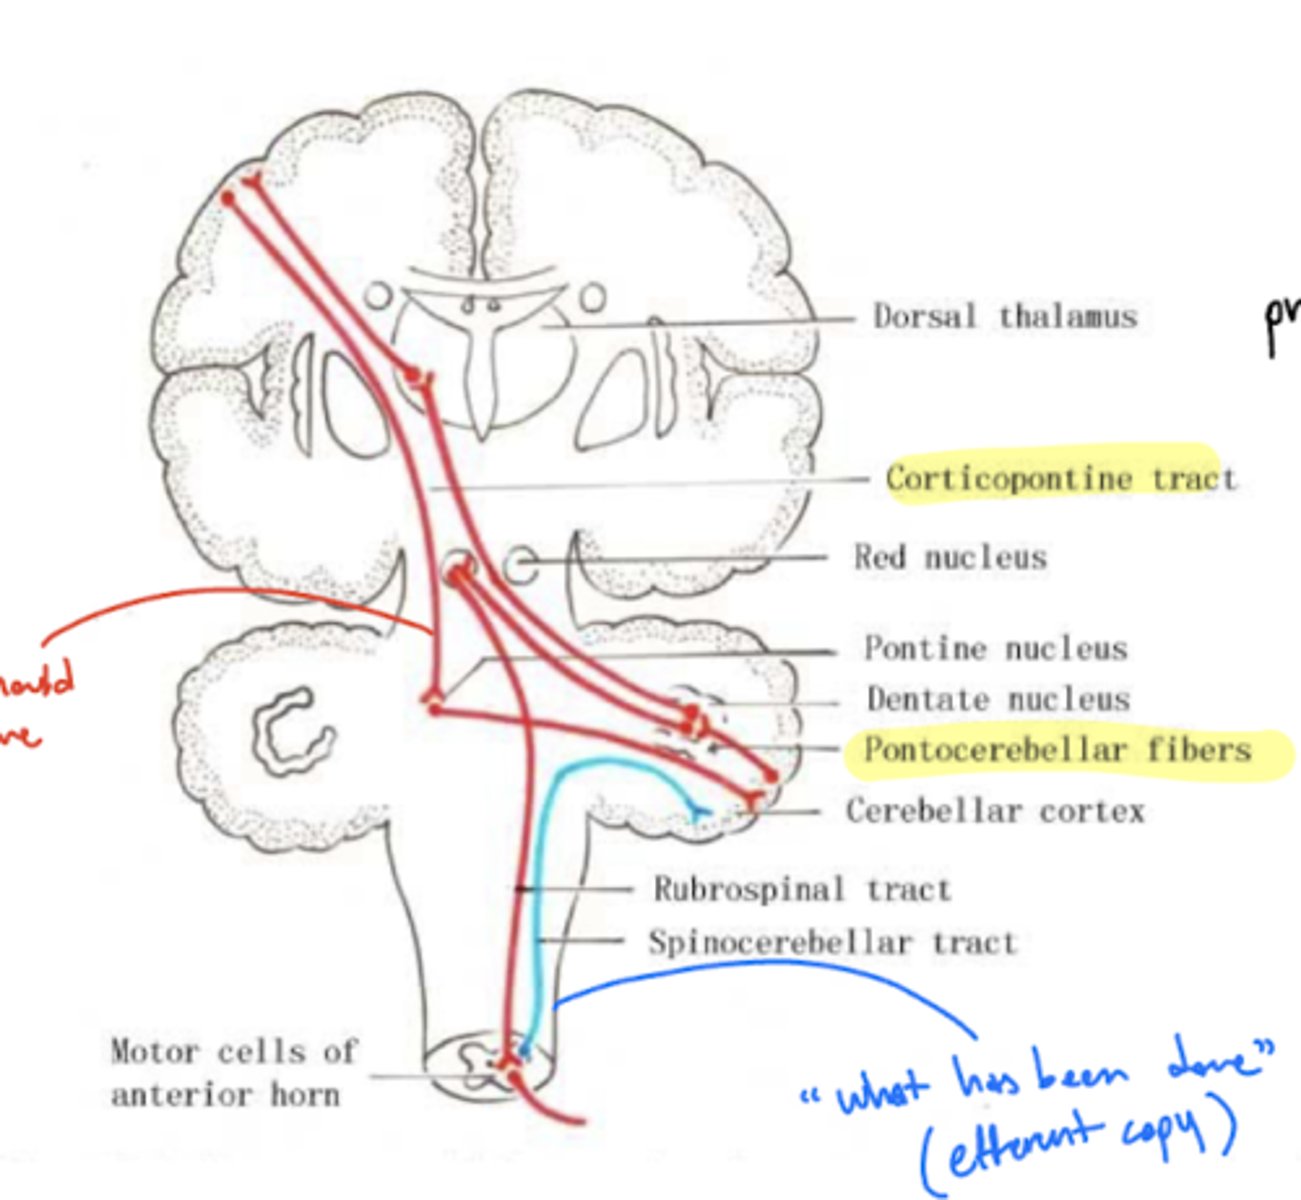

pontine nuclei

What is the pontine nuclei?

gray matter centers connecting the cerebral cortex and cerebellum -- coordinate voluntary motor output

What is the pontocerebellar tract?

a group of second order neuron fibers that run from the pons to the contralateral cerebellum, crossing to the other side of the pons and passing through the middle cerebellar peduncles

What do the pontocerebellar tract fibers do?

pontocerebellum controls and plans precise dexterous movements of the extremities, especially in the arm, forearm, and hand, and the timing of these movements

What is the pathway of fibers from the cortex to the cerebellum?

1. Corticopontine fibers (longitudinal fibers)

2. Synapse in the pons

3. Decussation (transverse fibers)

4. Middle cerebellar peduncle

5. Projection to the cerebellum

Where does the cerebellum send its copy of voluntional movement corrections?

1. thalamus -- additional processing

2. red nucleus -- projects down spinal cord to limbs for real time corrections

What are the two types of proprioception?

1. conscious -- goes into cortex (3, 1, 2)

2. unconscious -- goes to cerebellum (ipsilateral)

unconscious -- blue line